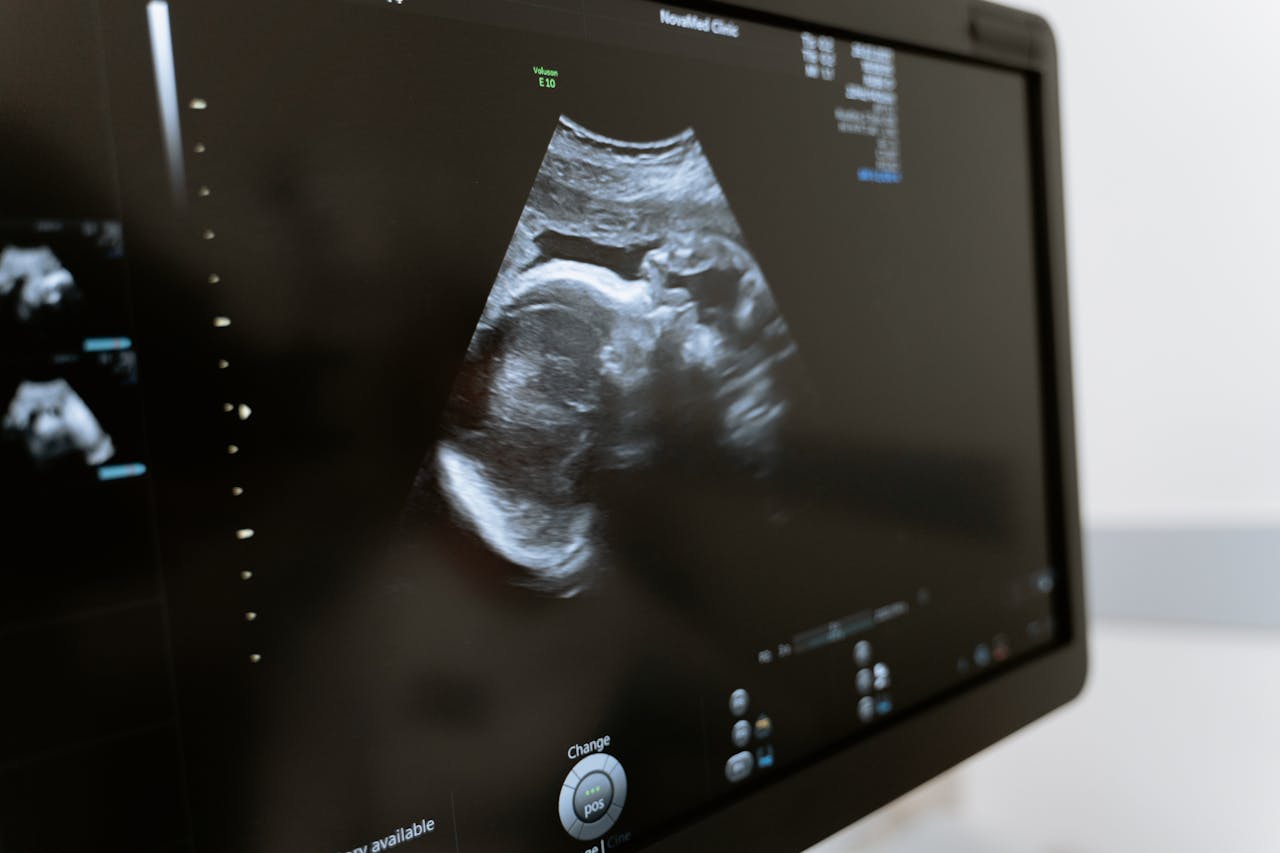

What Does a 15 Week Ultrasound Look Like?

Even though you’ve probably already seen your baby earlier, it doesn’t get less exciting to see them again. So, as you’re getting closer to having your ultrasound 15 weeks pregnant, you must be wondering what you will be able to see.

The good news for everyone who had their first-trimester ultrasound very early is that a 15 week ultrasound can show you much more. Your baby at 15 weeks ultrasound already has a distinguished head, torso, and limbs with tiny fingers and toes. That is, you will see a more recognizable human shape than before.

Another exciting news – your baby may start making the first facial expressions around 14 weeks. So, you can expect to see your baby smiling or expressing other emotions during your screening.

Lastly, you should know that babies are incredibly active at this time. They can occasionally suck their finger, stretch, or kick, and you might be able to see it in an ultrasound. And of course, this can be incredibly exciting, especially now when you will start feeling the first movements soon.